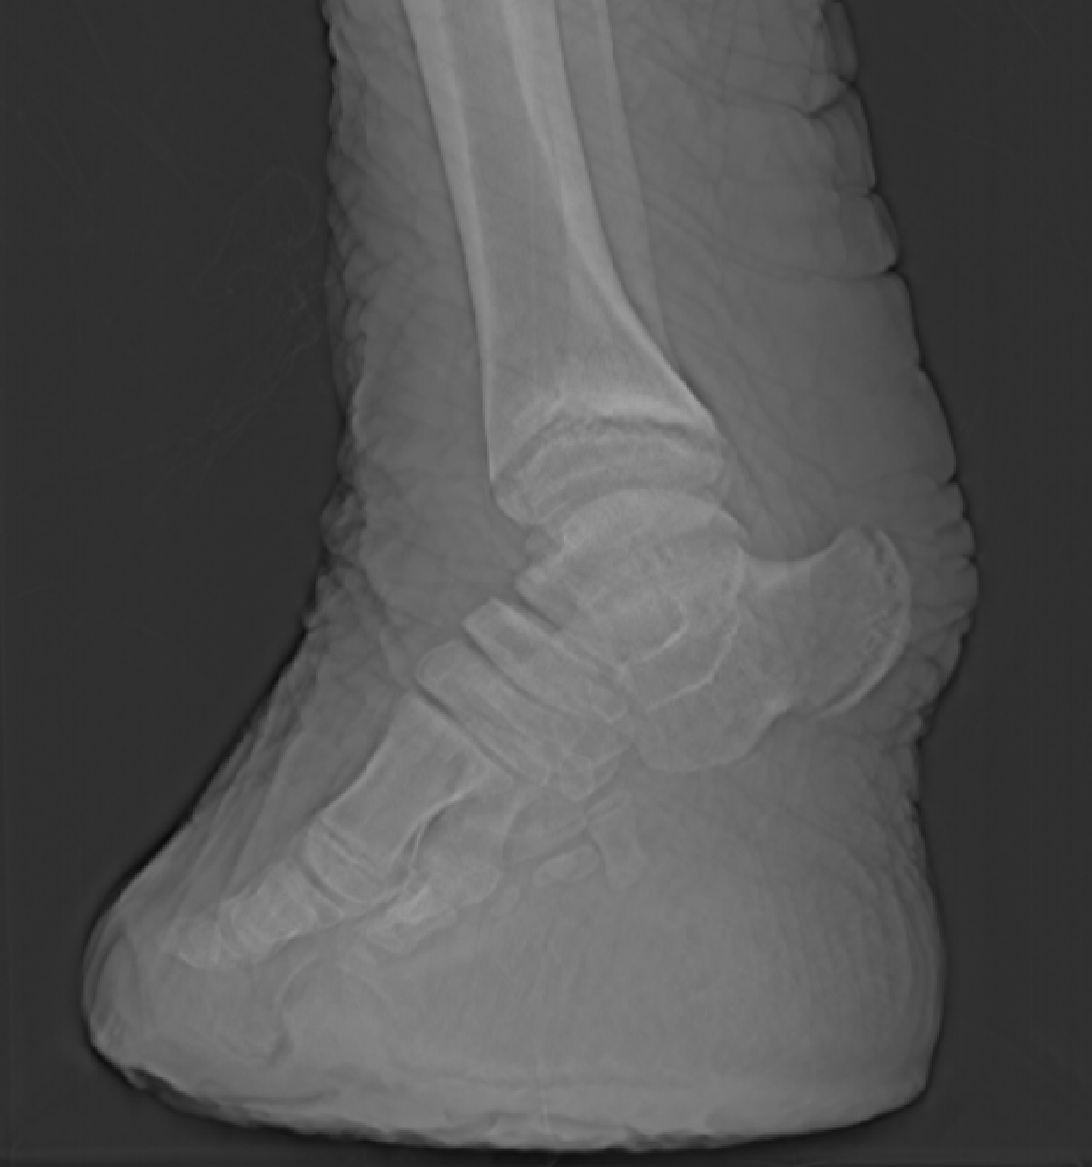

I still have time to do other things, too. Once in a while, a cool critter manifests in The Freezers. Check out a hippo foot from a CT scan! It’s not my best scan ever (noisy data) but it shows the anatomy fairly well, and some odd pathologies such as tiny floating lumps of mineralized soft tissue here and there. Lots to puzzle over.

Read Full Post »